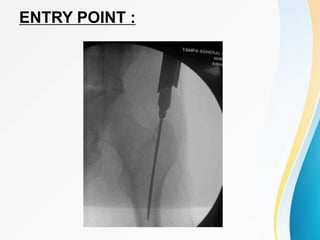

SKIN INCISION :

ENTRY POINT :